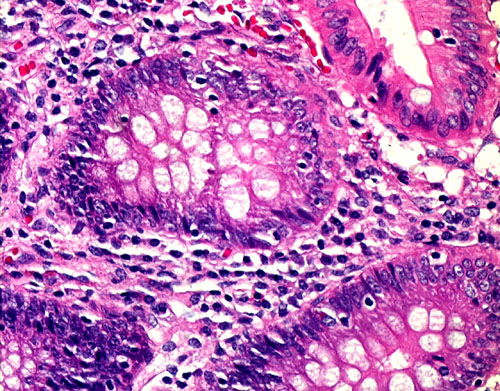

5. Accute Appendicitis

5-4-comp.JPG (160317 bytes)5-4.jpg (125873 bytes)5-10.jpg (168092 bytes)5-10b.jpg (141336 bytes)5-10c.jpg (148612 bytes)5-20c.jpg (125689 bytes)5-20b.jpg (103883 bytes)